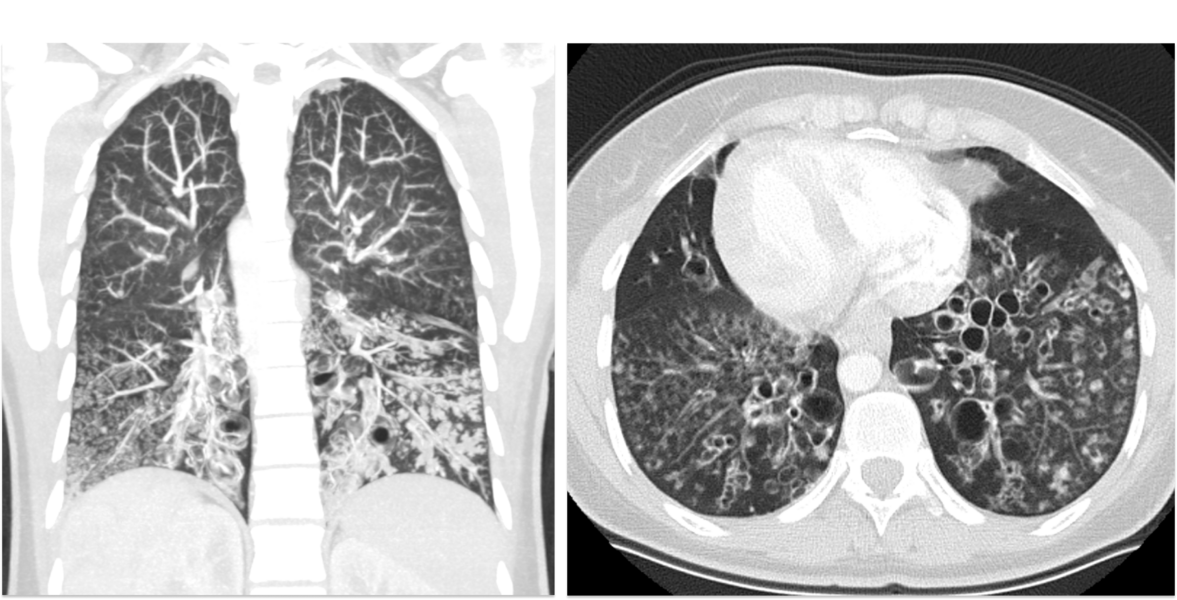

Identification of genetic causes for MMAF is rapidly increasing, whereas knowledge on molecular composition and function of associated components remains poorly understood. As sperm flagella and motile cilia comprise a similar axonemal structure, Primary Ciliary Dyskinesia (PCD), a mucociliary clearance disorder with recurrent airway infections, is closely associated with male infertility. Unfortunately, no evaluation of further disease manifestations, such as lung disease in MMAF males or fertility status of PCD males, is systematically performed.

Our recently published data and preliminary work demonstrate that several MMAF individuals additionally show a respiratory phenotype (e.g. SPEF2), and distinct PCD variants display MMAF (e.g. CCDC39). MMAF and PCD males will be recruited for critical genetic, andrological, and pulmonological evaluation and molecular characterization of human sperm flagella and motile cilia. Translation of study results into patient care will improve diagnostics and make aware potentially associated symptoms in MMAF and PCD with substantial benefit for the patient, if e.g. lung disease is treated properly.